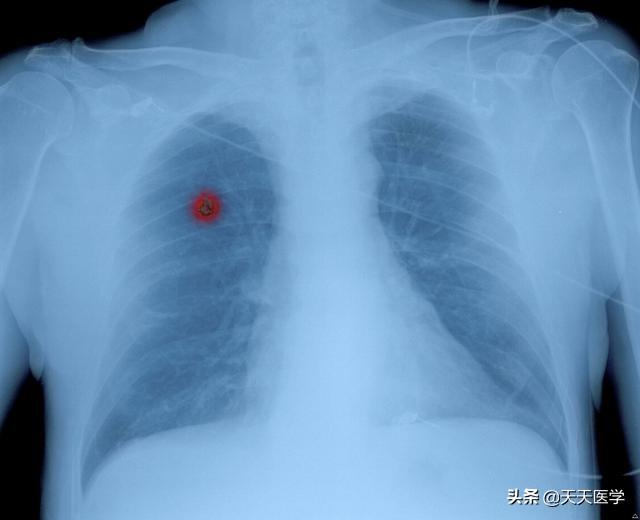

これらの体内信号の出現は、肺癌の可能性が非常に高いことを示している。次のような画像信号が再び現れたら、基本的に肺癌が近づいていることは明らかです。

- 胸部CTは現在、最も効果的な肺癌スクリーニング法である。胸部CT検査で、肺葉徴候、バリ徴候、空胞徴候、気管支像、腫瘍絨毛動脈、血管切断・集塊徴候、胸膜陥凹・引きつれ徴候、偏心腔、すりガラス様病変、肺門腫瘤などの画像信号を伴う肺結節が認められた場合、基本的に肺癌が確定する。